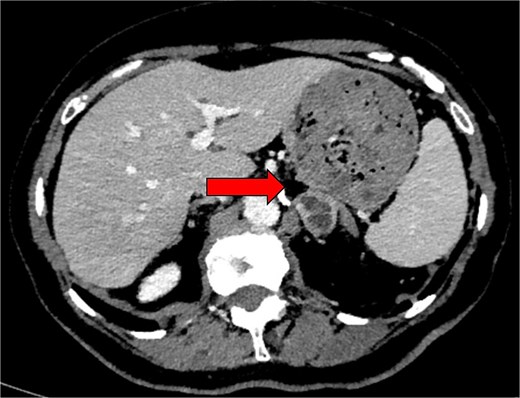

Computed tomography (CT) adrenal demonstrated a 2.8 × 2.6 cm left adrenal lesion (Fig. 2) that had increased in size when compared with the CT of 18 months prior (2.6 × 2.5 cm). The CT findings, combined with the clinical presentation and elevated plasma metanephrines, raised suspicion for a left phaeochromocytoma.

Preoperative axial CT image in 2024 showing an indeterminate left adrenal lesion measuring 28 × 26 × 13 mm, with heterogenous postcontrast enhancement and internal cystic change (indicated by arrow). Absolute and relative washout were calculated at 48.3% and 23.3%, respectively.